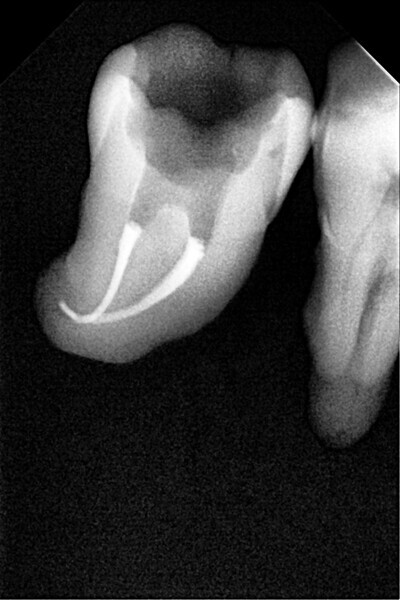

1. direct restoration using a fibre-reinforced flowable composite and membrane cube after endodontic treatment (Figs. 21–35); and

The second step focuses on reinforcing the restoration through careful fibre and FRC selection and placement. Tooth preparation should involve minimal removal of tooth structure to preserve as much natural tooth as possible in preparing the cavity for the restoration. Fibres or layers of FRC (flowable, paste, cube, etc.) are then strategically placed within the prepared tooth and composite material to reinforce areas susceptible to high stress and occlusal forces based on occlusal contact mapping. This strategic selection and placement of fibres and layers of FRC is crucial for enhancing the strength and longevity of the restoration.

Restore

The third step is to restore the tooth to its natural form, function and aesthetics. Composite resin, along with fibres or fibre-reinforced flowable or fibre-reinforced dentine substitute materials, is carefully applied to the prepared tooth structure. A layering technique is often used to ensure proper adhesion and integration of the reinforced materials with the composite material, enhancing the overall strength and functionality of the restoration. The composite resin is then polymerised using a curing light, ensuring that the materials are securely bonded within the restoration and providing a stable and long-lasting result. During this restorative process, the clinician should take special care not to expose fibres or FRC layers to the oral environment, as this can cause tissue irritation and water absorption by the materials in the long run. Therefore, the final layers of the restoration should always be a suitable aesthetic conventional composite resin.